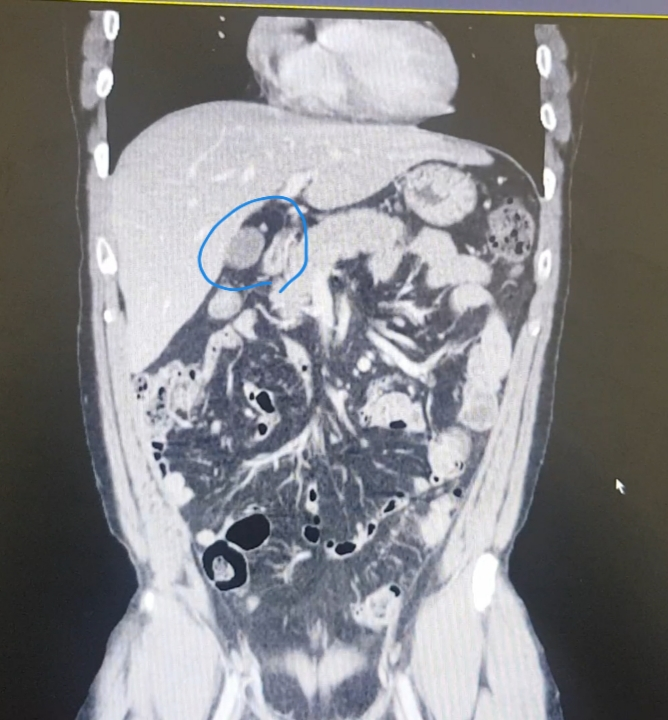

영상에서 이부분이 뭔지 알려주세요

간밑에 이게 뭔지 알려주세요

그리고 다른 질환이 보이는지 보이는거 알려주세요

특히 좌측복부 게실염 우측신장 물혹 있나봐주세요

우선 파란색으로 표시하신건 담낭입니다.

우측 신장에 물혹은 보이지 않습니다.

게실염은 제가 평소에 복부CT를 보는 의사가 아니라서 여부를 잘 모르겠습니다.